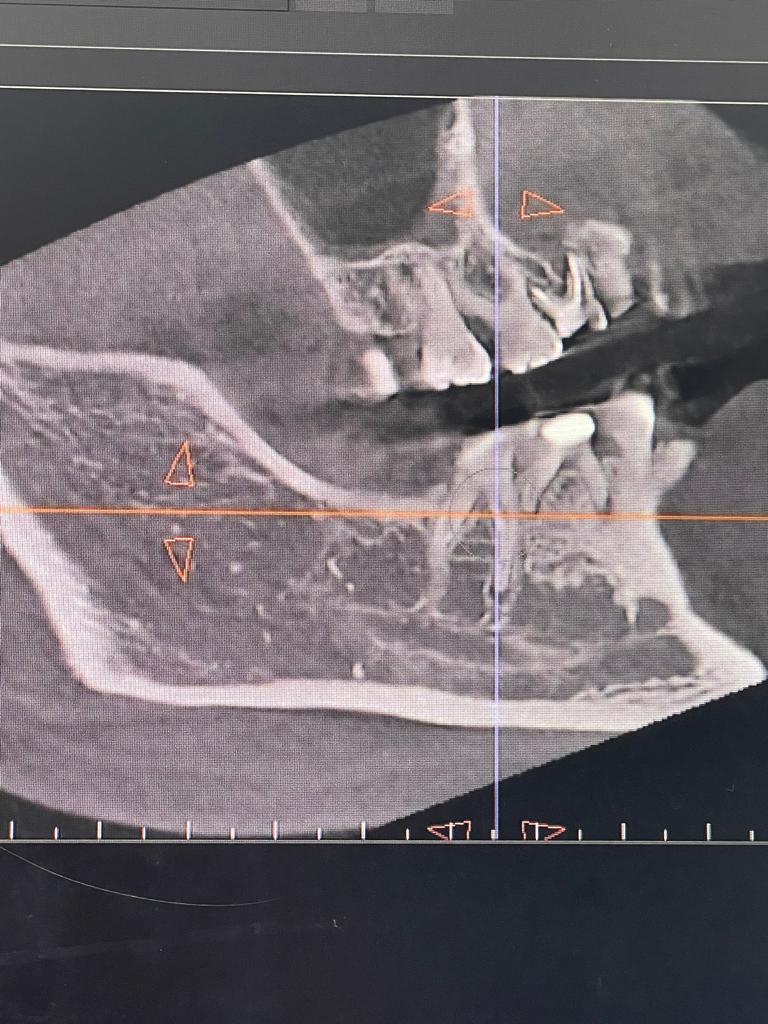

영구치가 선천적으로 결손된경우에는 유치를 최대한 오래 사용하시고 추후에 문제가 생기면 그떄는 임플란트 또는 브릿지 치료를 하시면될것같습니다.

유치는 영구치에 비해서 충치 저항성이 낮으며, 마모도 쉽게 일어납니다. 즉 시기의 문제일 뿐 시간이 지나면 유치에 문제가 생기며 발치를 해야하며 이러한 경우에 해당 부분을 수복해주는 방법은 임플란트 밖에 없습니다. 물론 앞 뒤 치아를 이용한 브릿지 등의 치료도 있습니다.

유치가 남아있다면 보통은 발치후에 임플란트를 하며 여러개인 경우 브릿지를 할 수도 있습니다.

미관상 앞니 옆 3개의 유치가 보기 좋지 않은 경우 발치를 하고 임플란트를 하거나 해당부위에 라미네이트로 치아성형을 하는 방법이 있습니다.

결손치료 인해서 해당 부위에 치아가 없다면 수복할 수 있는 방법은 임플란트나 브릿지 등으로 해서 치아를 만드는 것입니다. 브릿지는 정상적인 치아를 다듬어야 할 수 있기 때문에 임플란트가 우선적인 치료 방법이 될 수 있을 것으로 보입니다. 자세한 확인을 위해서 치과에서 진료를 받아보세요.